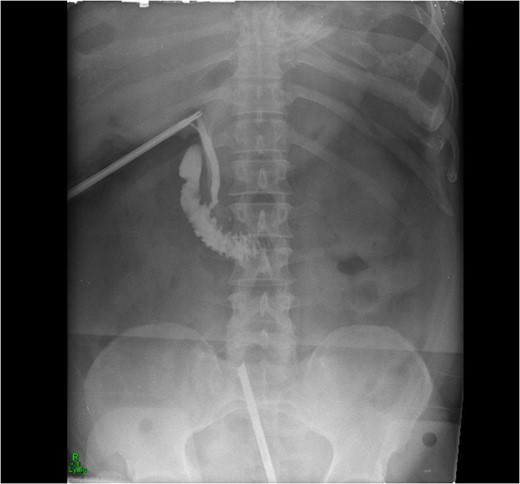

Intra-operative cholangiogram showing good flow of bile into duodenum.